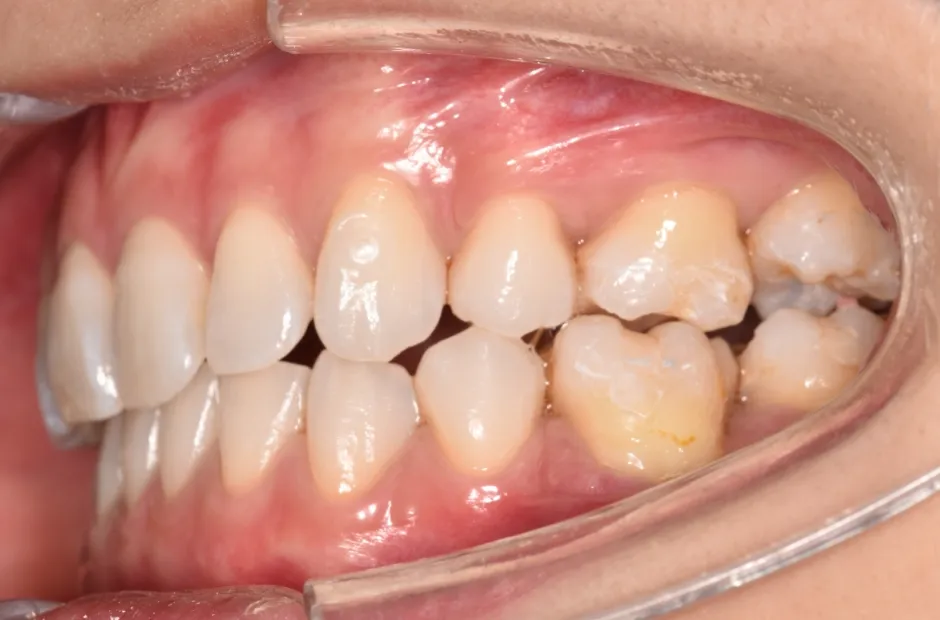

叢生

| 診断名・主訴 | 叢生 |

|---|---|

| 年齢・性別 | 43歳・女性 |

| 治療期間・回数 | 2年7か月 27回 |

| 治療に用いた主な装置 | 舌側矯正 |

| 抜歯部位 | 両顎4,4 |

| 治療費 | 100万円(税抜) |

| リスク・副作用 | 装置による違和感・疼痛・歯肉退縮・歯根吸収・虫歯のリスクなど |

治療前

治療中

治療後